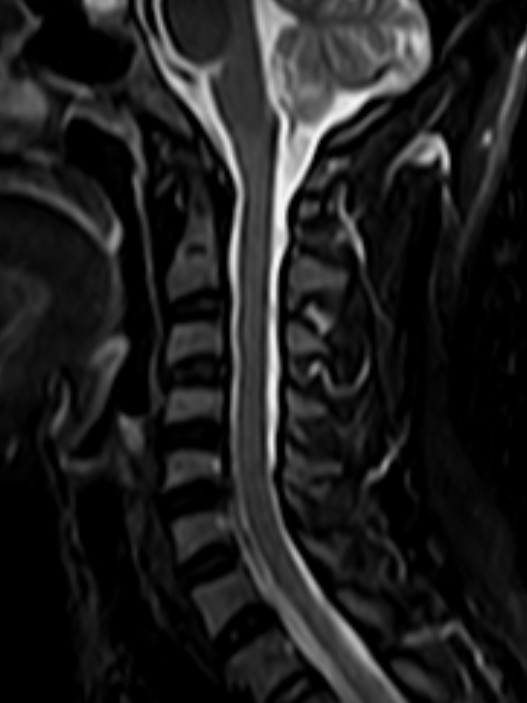

颈椎-STIR

1524110739454333.jpg